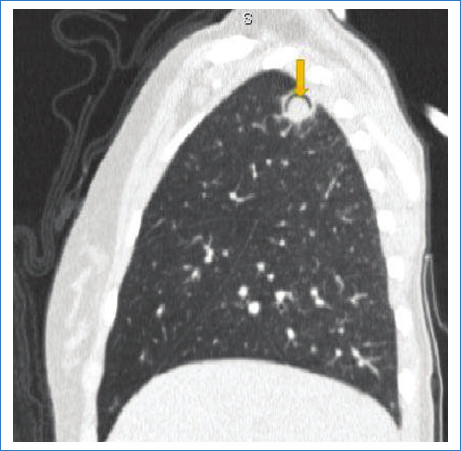

El signo del menisco pulmonar también se ha descrito como el signo del aire creciente o el signo de media luna. Corresponde a una colección de aire en forma de luna creciente que se visualiza en la radiografía y en la tomografía de tórax como una radiolucencia dentro de un área de consolidación o un nódulo; puede variar de forma, de media luna hasta encapsular totalmente la lesión (Fig. 1). Este signo radiológico, que no es patognomónico de aspergilosis, fue descripto en el año 1975 inicialmente por Bard y Hassani, quienes explicaron en un hematoma pulmonar el signo de la media luna, y en 1979 Curtis describió este signo como una forma invasiva de aspergilosis1.

Aspergillus es un hongo filamentoso conformado por cadenas celulares llamadas hifas. Fisiopatológicamente, estas alteran las paredes de los vasos sanguíneos a través de las arterias bronquiales generando oclusión de la luz vascular, lo que lleva a la necrosis y cavitación. Esto se refleja radiológicamente como un área de vidrio esmerilado, consolidación y/o nódulos peribronquiales. En su evolución el centro infartado se retrae y se reabsorbe, resultado de la reacción neutrofílica, dejando un área de tejido desvitalizado que se desprende del resto de la consolidación2. El aire que se encuentra entre el tejido desvitalizado y el parénquima consolidado que lo rodea tiene forma de media luna o del aire creciente (Fig. 2). Este signo es tardío, coincide con una recuperación progresiva de la infección y depende de la función leucocitaria, por lo cual generalmente se observa en pacientes inmunocomprometidos, que en general inician clínicamente con cuadro de hemoptisis3.